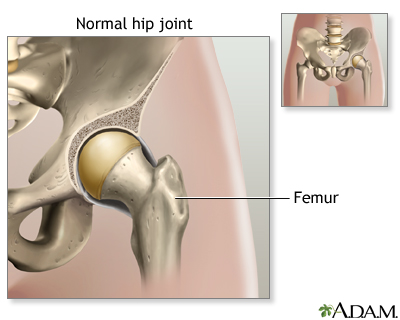

Your hip joint is made up of 2 major parts. One or both parts may be replaced during surgery:

- The hip socket (a part of the pelvic bone called the acetabulum)

- The upper end of the thighbone (called the femoral head)

Diseased hip - illustration

Diseased hip

illustration